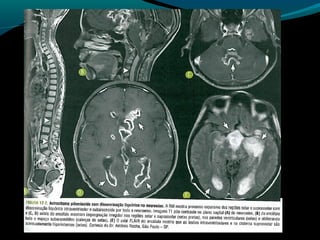

Astrocitoma pilomixoide

Semelhante ao pilocítico;

Comportamento mais agressivo;

Na infância pode ocorrer em qualquer estrutura do

SNC mas predomina no hipotálamo;

Precoce, crianças de 18 meses;

Pode acometer adultos mais frequentemente;

Sintomas: achados de aumento da pressão

intracraniana e compressão encefálica;

Retardo no desenvolvimento, vômitos, dificuldade de

alimentar-se ou aumento do perímetro cefálico;

Hipotalâmica;

TC

Lesão expansiva sólida na região hipotalâmica

quiasmática;

Isodensa ou hipodensa; realce difuso;

calcificação <10% dos casos;

Hemorragia é mais comum quando comparado ao

pilocítico;

RM

Isointenso ou hipointenso em T1 e hiper em T2 e

FLAIR, realce pelo gadolíneo;

Regiões com alto sinal em T1 (hemorragia);

Componente cístico 50%

Disseminação leptomeníngea em até 15%;

Difusão: não tem restrição à difusão da água (DD:

PNET, germinoma, linfoma);